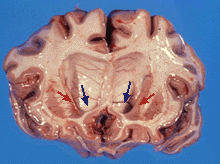

الإكلينيكي

Coronal brain section from a patient with HD showing dilatation of the ventricles (blue arrows) and atrophy of caudate nucleus (red arrows)